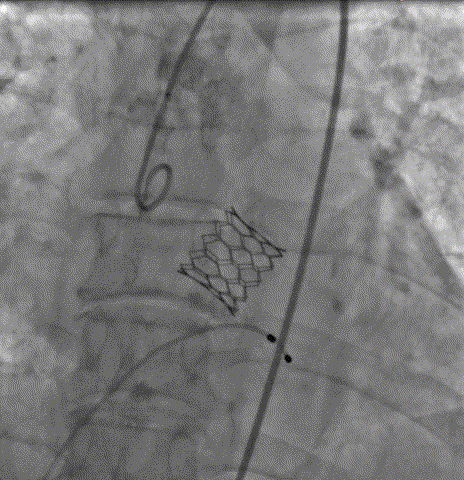

快速起搏下5atm精准球扩释放21#Renatus瓣膜

释放后造影示瓣膜位置理想,形态良好

通过术前精准评估,患者在全麻下行TAVR手术,DSA和食道超声双重引导,通过右侧股动脉建立工作路径,沿加硬导丝送入19mm*40mm球囊预扩张主动脉瓣,预扩张过程患者生命体征平稳,退出预扩张球囊后,利用可调弯输送器送入21# RENATUS瓣膜至升主动脉,猪尾巴导管再次造影确认位置。将21# RENATUS瓣膜顺利跨瓣,精准定位,精确释放,退出输送系统再次行主动脉根部造影,示瓣膜膨胀充分,无瓣口反流,无瓣周漏,冠脉血流正常,再次测主动脉根部压力及左心室压力,术后即刻平均跨瓣压差降至5mmHg,超声示术后峰值流速降至1.75m/s。瓣膜释放位置理想、形态及功能良好,瓣叶启闭良好,无外周血管损伤。